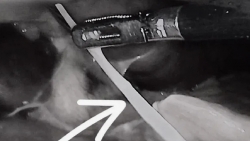

Bệnh nhân L.T.D. (77 tuổi, ngụ Long An) lên cơn đau bụng dữ dội vùng thượng vị, được chẩn đoán viêm phúc mạc do dị vật xuyên thủng dạ dày.